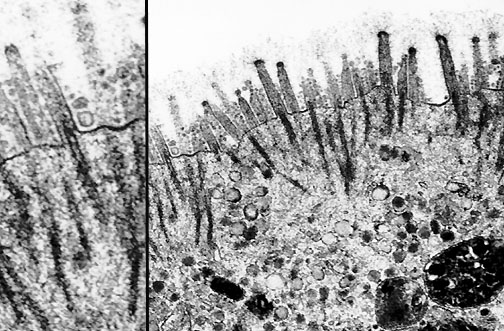

Microvilli are seen here in cell from an adenocarcinoma of the colon. The inset shows the dense core rootlets below and the rounded glycocalyceal bodies in the villi above in this electron micrograph.